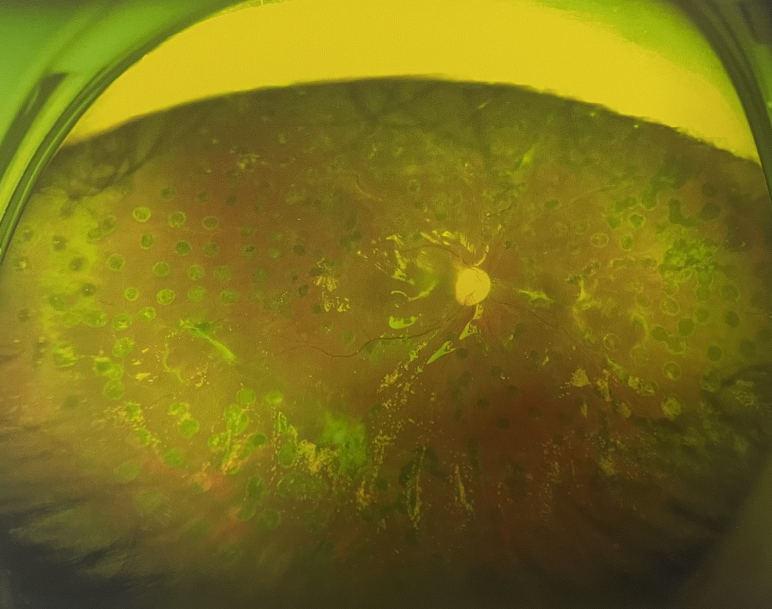

右眼術(shù)后

由于王女士的左眼沒有聽從醫(yī)生盡快做手術(shù)的建議,一直耽誤,從4月前的0.4視力逐漸下降到僅剩眼前手動,導(dǎo)致左眼發(fā)展到糖尿病視網(wǎng)膜病變VI期(屬于6期糖網(wǎng)中的晚期),已經(jīng)產(chǎn)生大量新生血管+纖維增值+廣泛牽拉性視網(wǎng)膜脫離,由于耽誤了病情,且病情發(fā)展異常迅速,導(dǎo)致目前左眼連保住眼球都很困難。

“而如果4月余前,左眼及時手術(shù)(當時左眼病情比右眼輕,增殖膜還未累及黃斑),左眼將恢復(fù)的比右眼還好,甚至可以恢復(fù)到0.8或1.0,而現(xiàn)在連保住眼球的機會都很渺茫”,張小虎醫(yī)生表示實在可惜。

4個月前的左眼